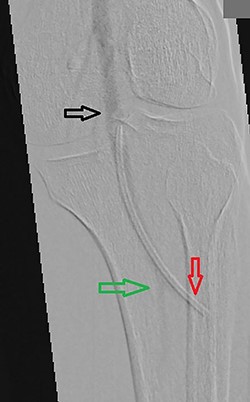

Perioperative contrast imaging showing the popliteal artery (black arrow) and the posterior tibial artery (green arrow) with the tip of the catheter embolus in the anterior tibial artery (red arrow).